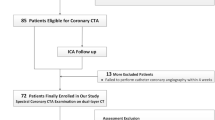

One hundred three patients referred to coronary CTA with suspicion of CAD were investigated on a dual-layer spectral detector CT (SDCT) scanner. CACS was calculated from both TNC and VNC images by software certified for medical use. Patients with a CACS of 0 were excluded from analysis.

Approval of the Institutional Review Board had been obtained prior to this study. Written informed consent was waived for this retrospective analysis of routinely acquired imaging and clinical data. All patients who underwent CACS and coronary CTA due to suspected CAD using spectral CT at our institution were eligible for the study. All patients without calcified plaques in true non-contrast (TNC) images (corresponding to a calcium scoring of 0) were excluded from statistical analysis.

One hundred three consecutive patients with suspected CAD were scanned using the dual-layer SDCT system between January 2018 and March 2020. Fifty-five patients (53.4 %) were referred to coronary CTA for atypical cardiac symptoms, 26 patients (25.2 %) for typical cardiac symptoms, and 22 (21.4 %) for evaluation of operability. Out of the study population, 32 patients (31.07 %) were diagnosed with obstructive coronary artery disease. Thirty-one patients were excluded from primary statistical analysis due to calcium scoring of 0 as determined by the TNC images. Twenty-three of these patients had a CACS of 0, three of these patients had a CACS of 1, four had a CACS of 2, and one had a CACS of 4 using the VNC data. Forty-eight of the remaining 72 patients were male (66.7 %). The mean age was 61.3 ± 10.8 years (IQR: 54.4–69.0 years; range: 36–85 years).